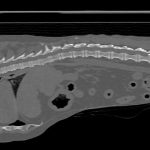

雑種猫の交通事故による骨折と皮膚剥奪症の治療

交通事故は、受傷部位によって様々な症状を引き起こす。受傷した臓器と、受傷の程度を調べるとともに状態を安定化させることが重要といえる。